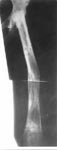

1.Остеобластокастома верхней трети бедра (возраст 24 года)

2.Резекция проксимального отдела бедра с остеомией в нижней трети в аппарате Илизарова

3.На этапе замещения

4.Артродез тазобедренного сустава с доудлинением бедра

5.Результат лечения